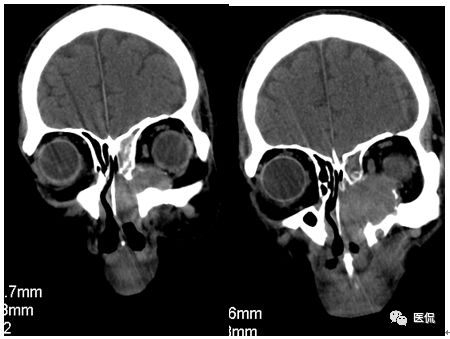

冠状位平扫

CT平扫及增强示:左侧上颌窦及鼻腔可见软组织密度影,呈膨胀性生长,周围骨质压迫性吸收破坏,累及左眶,病灶密度不均匀,周边区可见点状钙化,增动脉期轻度强化,局部见小灶性稍高密度区,静脉期病灶内见不均匀明显强化,CT值最高达117HU,延迟期强化范围有所增大。